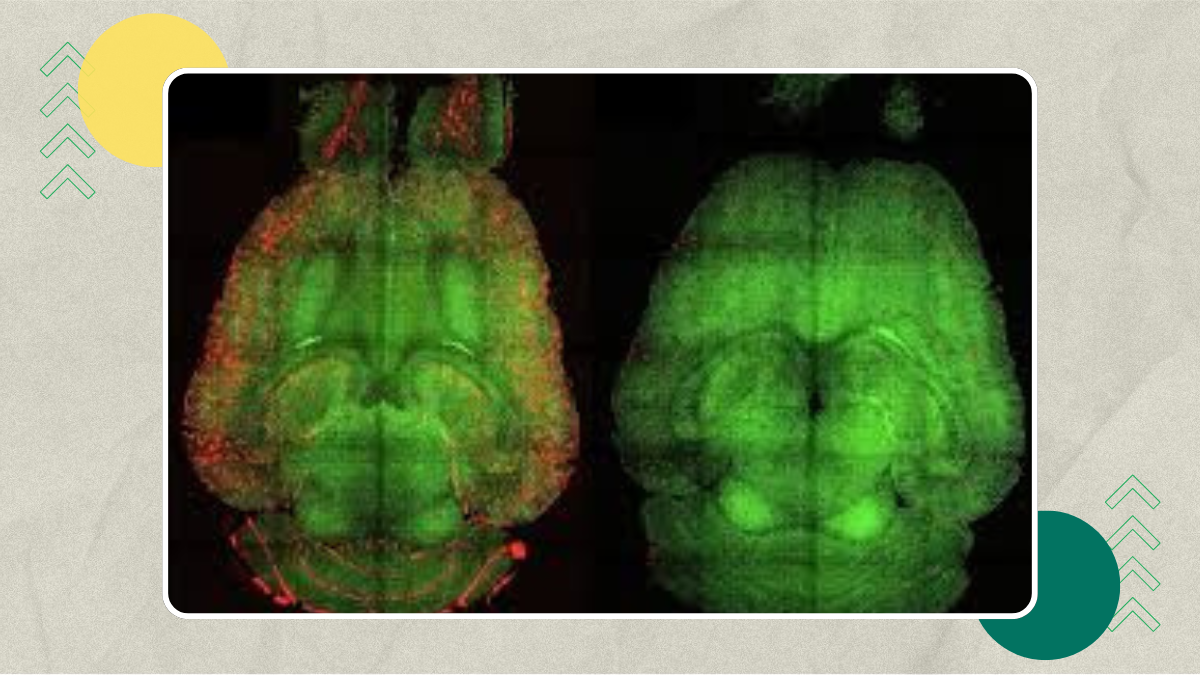

في إنجاز علمي يفتح باب الأمل أمام ملايين المصابين بمرض الزهايمر حول العالم، تمكن فريق دولي من الباحثين في معهد **الهندسة الحيوية في كاتالونيا (IBEC)** بالتعاون مع **مستشفى غرب الصين بجامعة سيتشوان** من **عكس أعراض الزهايمر في الفئران بعد ثلاث حقن فقط باستخدام جزيئات نانوية ذكية**. المدهش في الأمر أن العلاج الجديد لا يستهدف الخلايا العصبية مباشرة، بل يعيد **ترميم الأوعية الدموية الدماغية** واستعادة أدائها الطبيعي، وهو توجه علاجي غير مسبوق في هذا المجال.

نتائج مبهرة بعد حقن قصيرة المدى

حقق العلماء **انخفاضاً بنسبة 60٪ في تراكم بروتين الأميلويد خلال ساعة واحدة فقط** من الحقن الأولى، وهو رقم مذهل بالنظر إلى سرعة الاستجابة. وبعد متابعة الفئران لمدة ستة أشهر، لاحظ الباحثون أن الفئران المسنة التي عولجت استعادت سلوكاً طبيعياً شبيهاً بالفئران السليمة. هذه النتيجة ترجّح أن التأثير العلاجي طويل المدى ناجم عن **إصلاح المنظومة الوعائية الدماغية**، وليس عن تفاعل عصبي مؤقت.